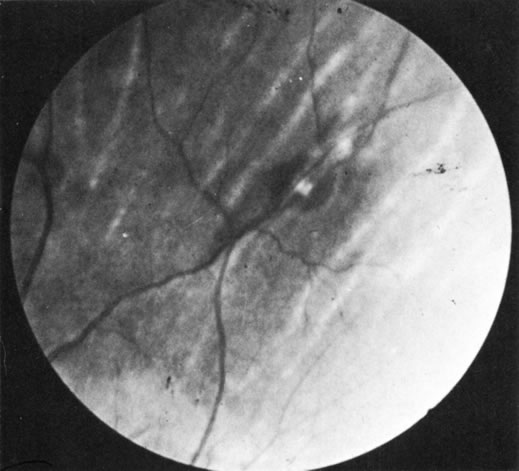

Sarcoidosis is a multisystem disease of unknown cause but with a number of immunologic defects. It can affect almost any organ, but the principal targets are the lungs and lymph nodes. Ocular lesions—most commonly iridocyclitis, but also eyelid and conjunctival nodules, keratitis, and retinal, optic nerve, and orbital lesions—occur in approximately 26% of cases (Figs. 1, 2, 3, 4, and 5). An ocular syndrome with the characteristics of sarcoidosis but lacking systemic disease also has been seen.

Fig. 4. Candle wax exudates in sarcoidosis. (Courtesy of Dr. R. Weinberg.)